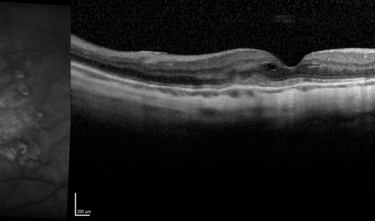

Clase 20 - Signos clave en patología traccional vítrorretiniana

Clase 21 - Desprendimiento de vítreo y desprendimiento de retina

Clase 15 - Depósitos y signos específicos en DMAE no neovascular

Clase 18 - Signos estructurales diferenciales entre neurodegeneración y exudación en DMAE